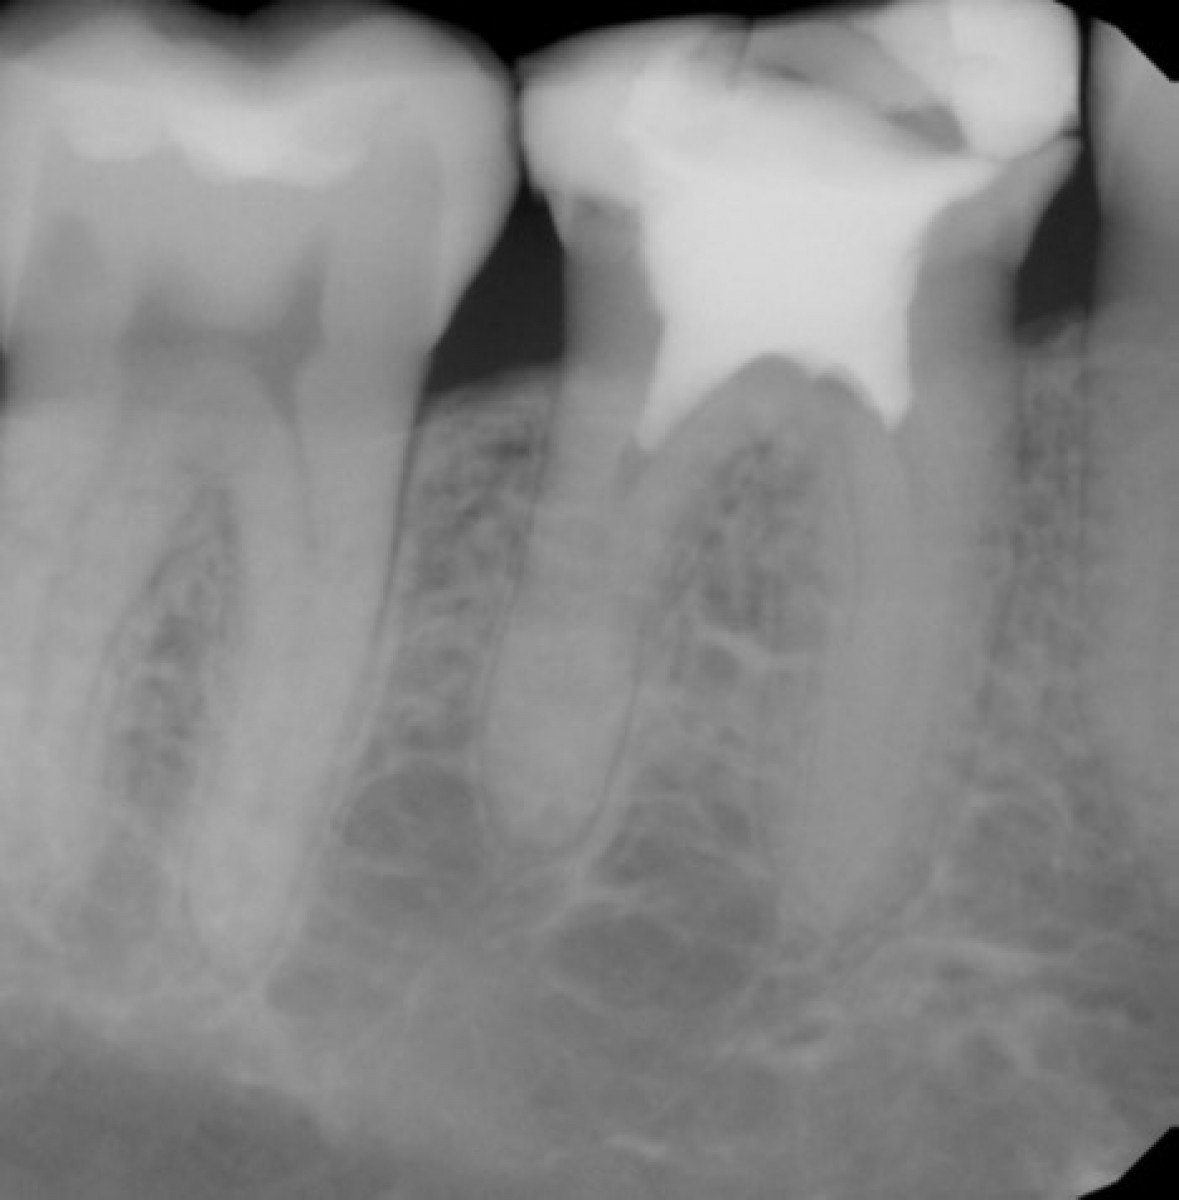

A 56 years-old patient came to our office complaining of an intense pain on tooth 3.8. The elements how next ended carious lesion (Fig. 15) and the x-rays confirmed that the decay was in proximity to the pulp chamber (Fig. 16). A lower alveolar nerve block was executed, then rubber dam was placed and the decay was removed with the help of a microscope (Fig. 17-19). After removing all the decayed tissue, the access cavity was completed trying to be extremely conservative and the root canal openings were found and enlarged with the help of ultrasonic tips (Fig. 20). The scouting of the root canal was executed with thin hand files (Fig. 21, 22), then the shaping procedure was carried out by means of reciprocating NiTi files (Fig. 23, 24) 9. The irrigation phase was executed with IrriFlex, a novel polypropylene irrigation tip that has a 2-side vented exits (Fig. 25-27), then the irrigant activation was done with sonic tips. Shaping and irrigation were alternated until the root canals were looking clean and appropriately tapered (Fig. 28-32) 10, 11. Paper cones were then used to dry the root canals (Fig. 33, 34) then, in this case, the obturation was done with single cone and bioceramic sealer (Fig. 35, 36). The access cavity was sealed with composite material, then an indirect restoration was booked.